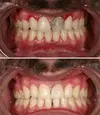

Gum Bleeding

Tooth and Gum Diseases

Zirconium Applications

Porcelain Applications

Laminate Veneer